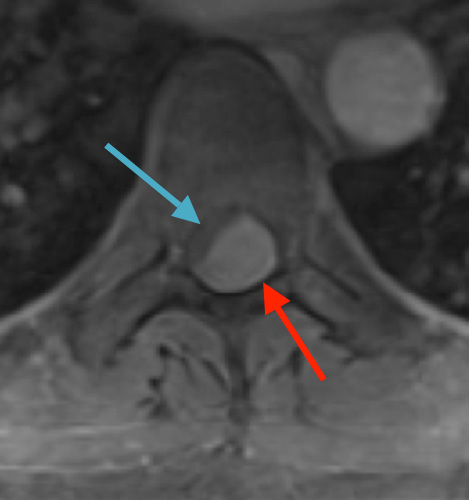

Postoperative MRI T2 illustrating the restoration of CSF surrounding the cord (blue arrow)